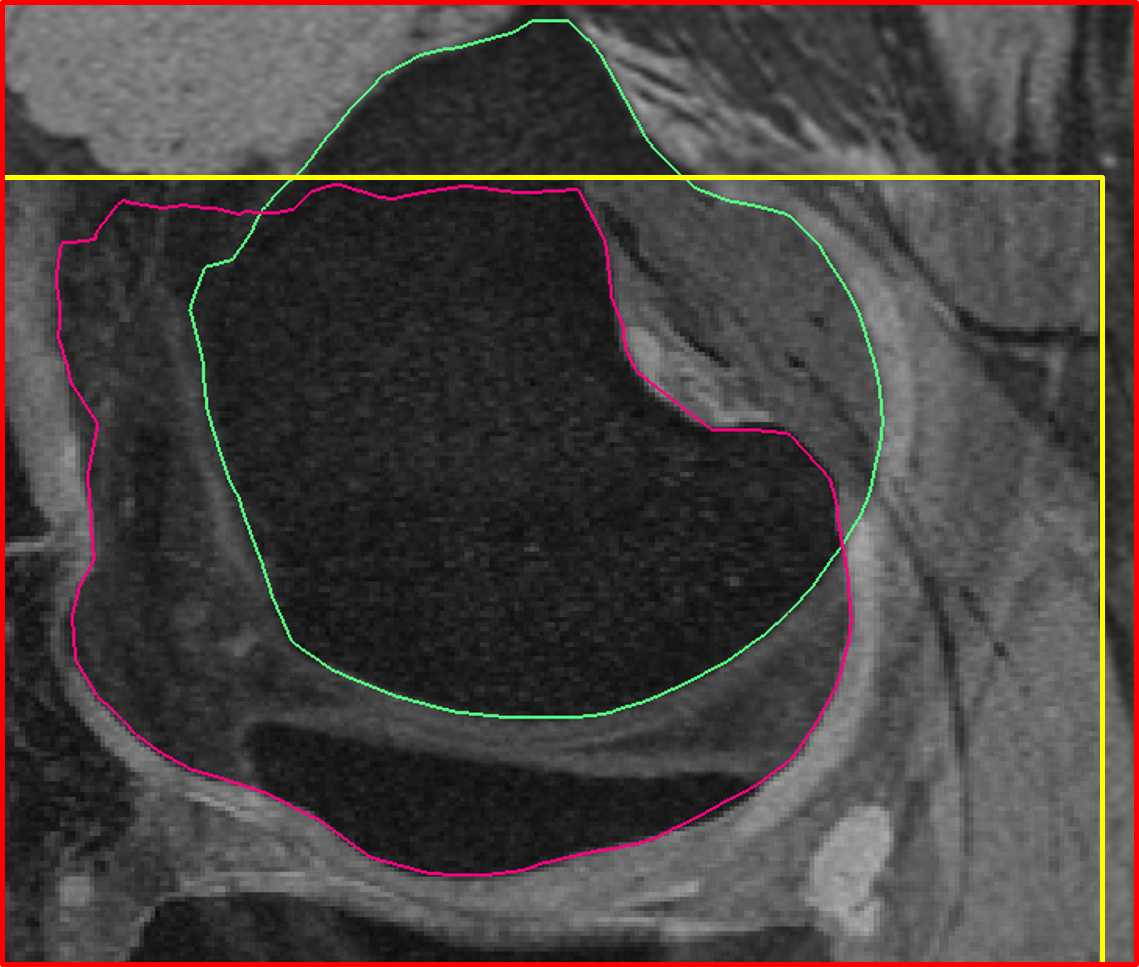

Fig. 7 qualitatively compares the segmentation accuracies between the gradient-based costs and the hierarchical classifier with respect to the independent standard. Both the femur and tibia are shown with their respective bone and cartilage segmentations showing good agreement between learning-based segmentation and the independent standard.

Fig. 8 qualitatively shows the improvement of 4D LOGISMOS over 3D. Note the lack of an obvious edge distinguishing the tibia and femur cartilage. Using the spatial and temporal contextual information from all the time-points, the 4D method is able to correctly position the cartilage for the tibia and femur despite the lack of image information locally.